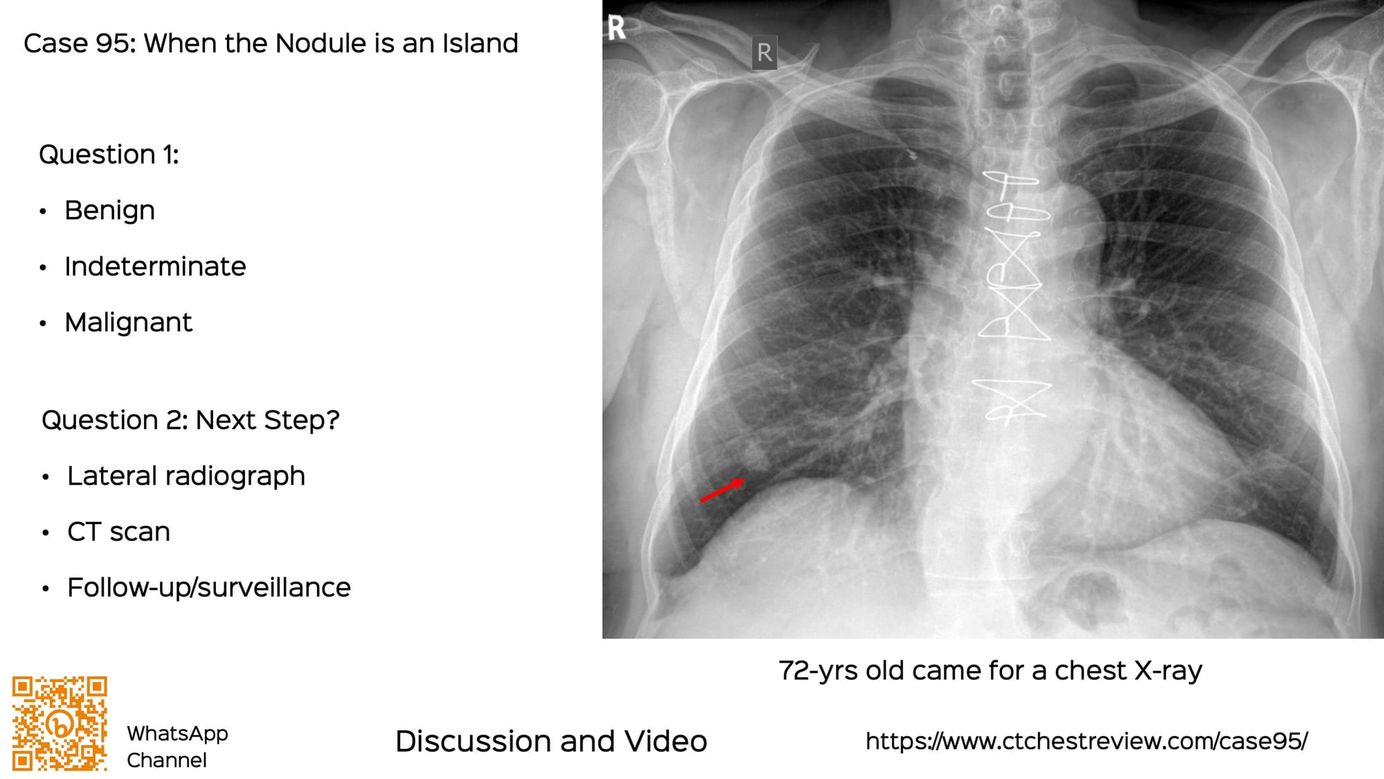

Case 95: When the Nodule is an Island Members Public

The first step, when a nodule is seen on a chest X-ray incidentally is to confirm its location...lung, pleura, chest wall, superficial...usually with a CT scan